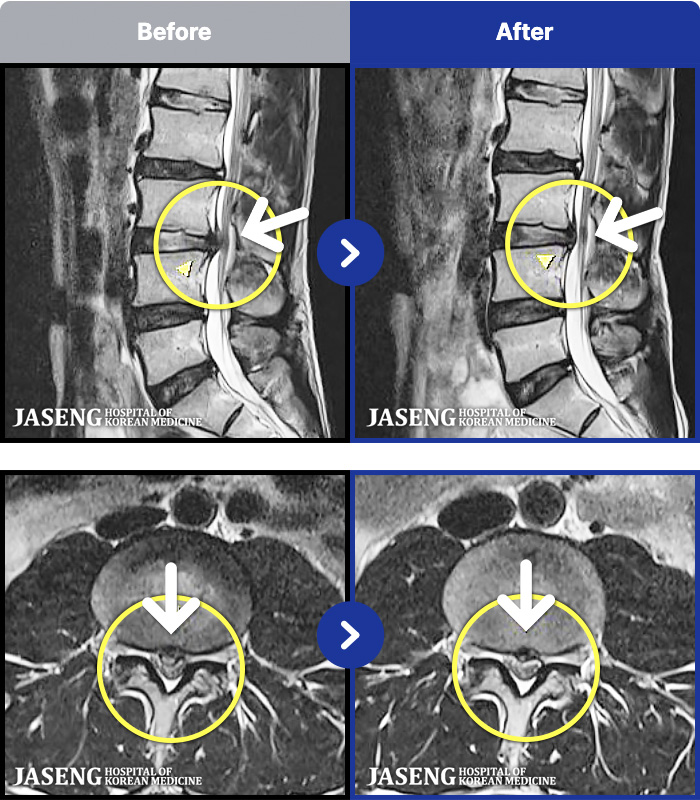

1,301 MRI ũ ʸ Ȯϼ.